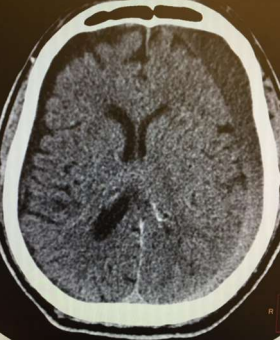

Fig 1,2,3,4,5,6,7,8,9,10,11,12,13,14,15

Thirty eight out of Eighty-two patients were treated conservatively and were studied (25 men; 13 females, mean age, 64.8 years). The average thickness of the hematoma was 18 mm, the mean midline shift was 4.7 mm, and the average attenuation value of bleed on computed tomography scan was 33.5. Thirty-eight were treated successfully with steroid treatment, whereas 44 patients required surgery. The female gender, less midline shift, less density (Hounsfield units) was noted to be associated with successful medical treatment. We propose a grading based on the total score given to the midline shift and density.

Figure 1

Figure 2

Figure 3

Figure 4

Figure 5

Figure 6

Figure 7

Figure 8

Figure 9

Figure 10

Figure 11

Figure 12

Figure 13

Figure 14

Figure 15